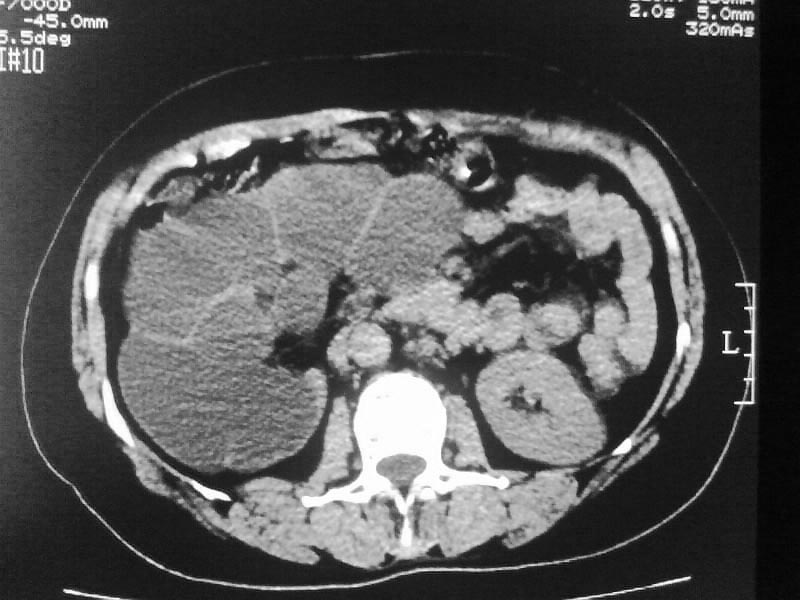

标题: CT20044:女,45岁,腰痛2年,双肾结石,右输尿管结石,右肾重度积 [打印本页]

标题: CT20044:女,45岁,腰痛2年,双肾结石,右输尿管结石,右肾重度积

其内见多房性分隔考虑多囊肾

多囊肾可以排除。

支持双肾结石、右输尿管上端结石,右肾重度积水

支持 右肾结石、右输尿管上端结石,右肾重度积水。